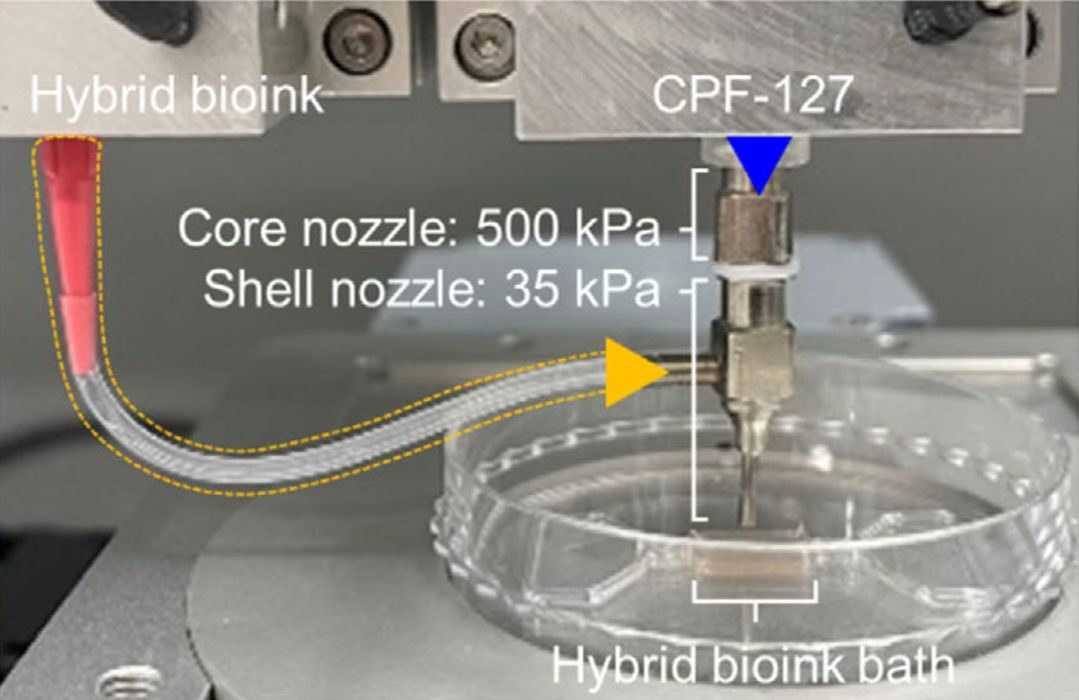

Researchers 3D Print Functional Blood Vessels Using Custom Bioink

Researchers have developed a method of 3D printing blood vessels, and that’s quite important.

New 3D Printed Blood Vessels Could Transform Heart Bypass Operations

Researchers at the University of Edinburgh have developed a method of 3D printing blood vessels.